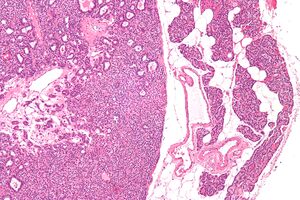

صورة مجهرية لغدوم الجار درقية (يسار) وغدة جارات درقية طبيعية (يمين). صبغة الهيماتوكسيلين واليوزين.

يتم تأكيد فرط نشاط جارات الدرقية عن طريق اختبارات الدم مثل مستويات الكالسيوم وهرمون الغدة الدرقية. اختبار محدد لغدوم الجار درقية هو التصوير الومضاني لغدة الجار درقية سيستاميبي. تكشف تقنية التصوير النووي هذه عن وجود وموقع أنسجة جارات الدرقية المرضية.[7]